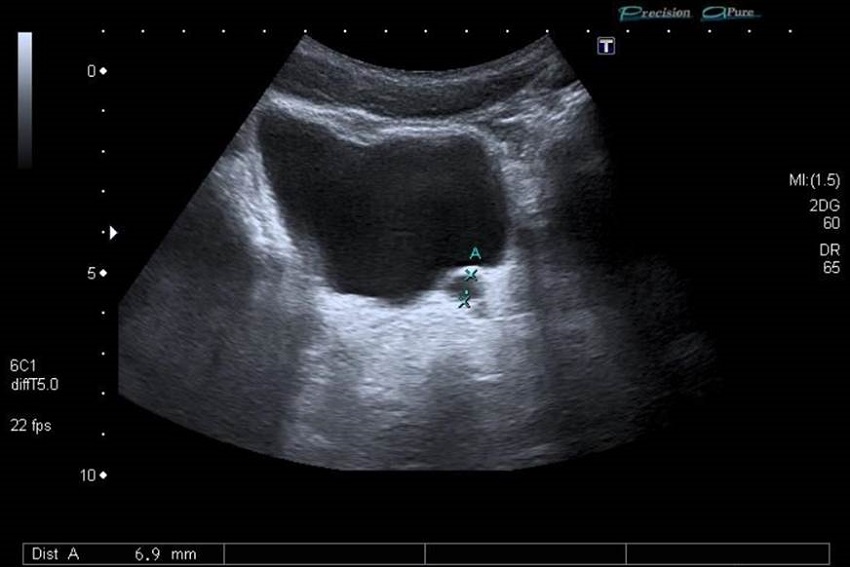

Se realiza la ecografía abdominal, donde se objetiva un riñón único derecho, no claramente compensador (figura 1). No se identifica el riñón izquierdo, pero se visualizan dos imágenes quísticas retrovesicales izquierdas, alargadas, que parecen desembocar en la próstata o el cuello vesical (figura 2). La más posterior, de 0,4 x 2,3 cm, probablemente corresponda a una dilatación de la vesícula seminal o del quiste mesonéfrico; el anterior, de 0,6 x 4,2 cm, podría corresponder a una dilatación del divertículo del remanente ureteral ciego con desembocadura baja (figura 3).